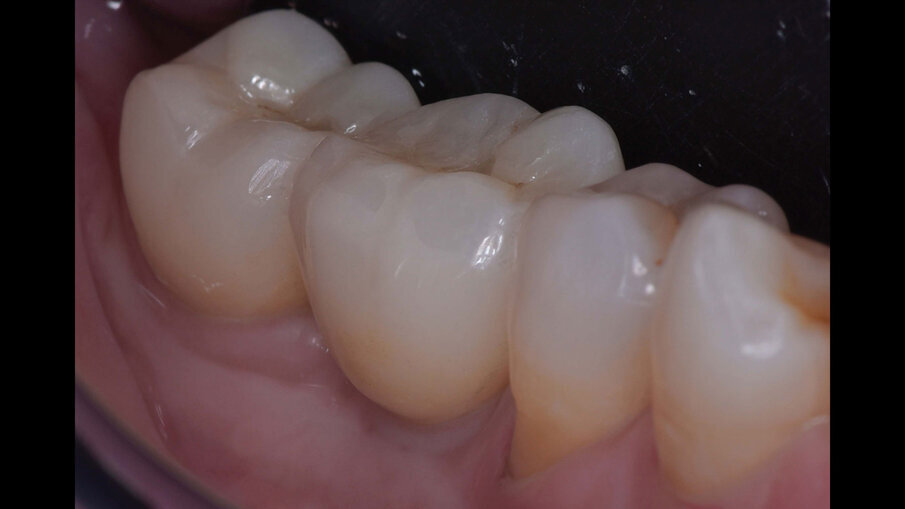

Dopo due settimane, è stata eseguita una scansione 3D con scan body e sono state consegnate due corone provvisorie avvitate sugli impianti, in modo da poter condizionare i tessuti molli peri-implantari (Figg. 11-12b). A causa di un’inadeguata banda di mucosa cheratinizzata sul versante vestibolare, è stato eseguito un intervento di vestiboloplastica con affondamento di fornice e innesto epitelio-connettivale prelevato dal palato (Figg. 13, 14). Dopo un’ulteriore maturazione dei tessuti, una nuova scansione ha permesso di dare informazioni all’odontotecnico circa il tragitto transmucoso ottenuto con i provvisori e sono state consegnate due corone definitive avvitate in zirconio (odt. Alessandro Giacometti; Figg. 15-19b). La paziente è stata seguita con controlli periodici clinici e radiografici a 6 mesi, 1 anno e 2 anni dal carico protesico (Figg. 20a, 20b).

Figg. 18a, 18b_Elementi definitivi in zirconio avvitati.

Figg. 19a, 19b_Immagine clinica e radiografica che mostrano il manufatto protesico finale.